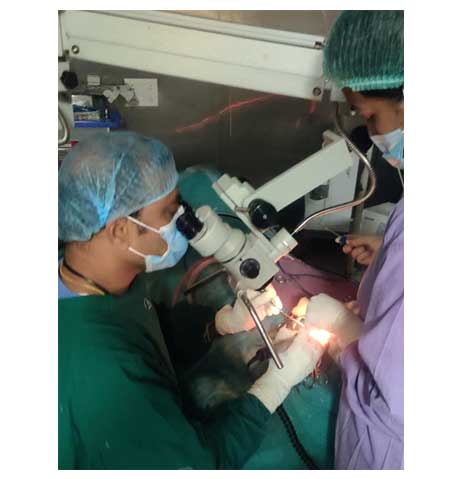

42/M Patient came with H/o self inflicted, cut throat Diagnosed -Self inflicted cut injury /zone-1 and 2 neck injury . Presented with severe bleeding, hypovolumic shock .Airway secured and fluids started . Pt was shifted to emergency OT and resuscitation started and stabilized by our anesthesia team. Patient underwent Emergency exploration of neck and bleeding IJV was ligated and ryles tube inserted .There were two penetrating wounds in neck , one in zone 1 which was exposed and Tracheostomy done. In zone 2, there was complete transection of thyroid cartilage and epiglottis, completely separated and tear went upto pyriform mucosa. Cartilage repair and mucosa repair done . It is first of its kind , cut throat injury with vessel bleed and pt revived in almost arrested stage and successfully surgical repair done .